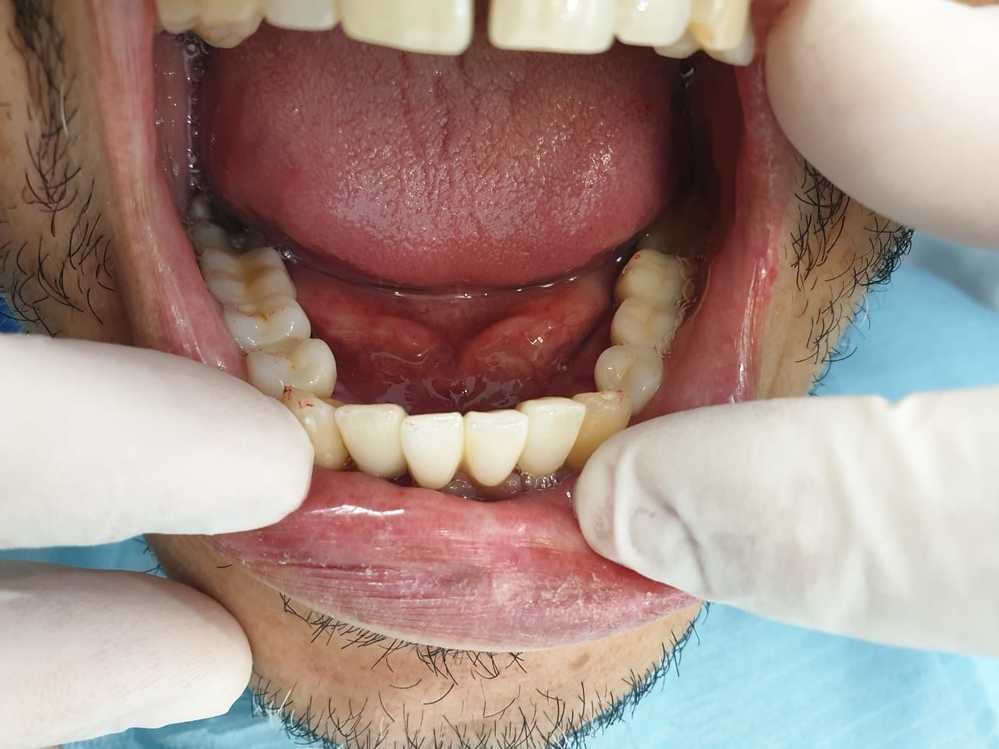

Protesi fissa su impianti in zirconio-ceramica

Protesi fissa su impianti in zorconio ceramica